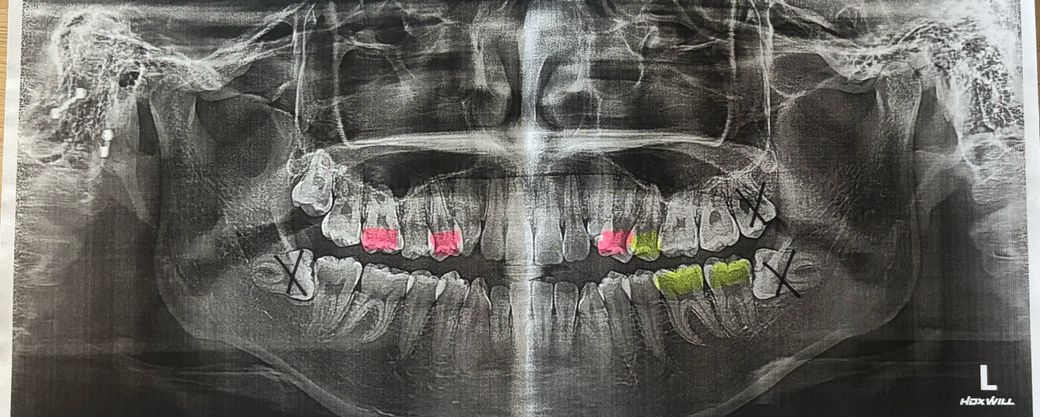

핑크색은 인레이, 노란색는 레진, x표는 발치할 사랑니입니다. 인레이는 신경치료 가능성 있다고 하셨어요

제 일정도 많고 예약도 밀려서 3/21에 예약 잡햤는데 괜찮을까요? 사랑니 발치로 예약잡긴 했어요. 사랑니랑 충치치료 동시에 못하죠??

지금 통증정도는 차가운거 먹으면 신경쓰이는 정도입니다. 양치랑 치실 열심히 하면 괜찮을까요